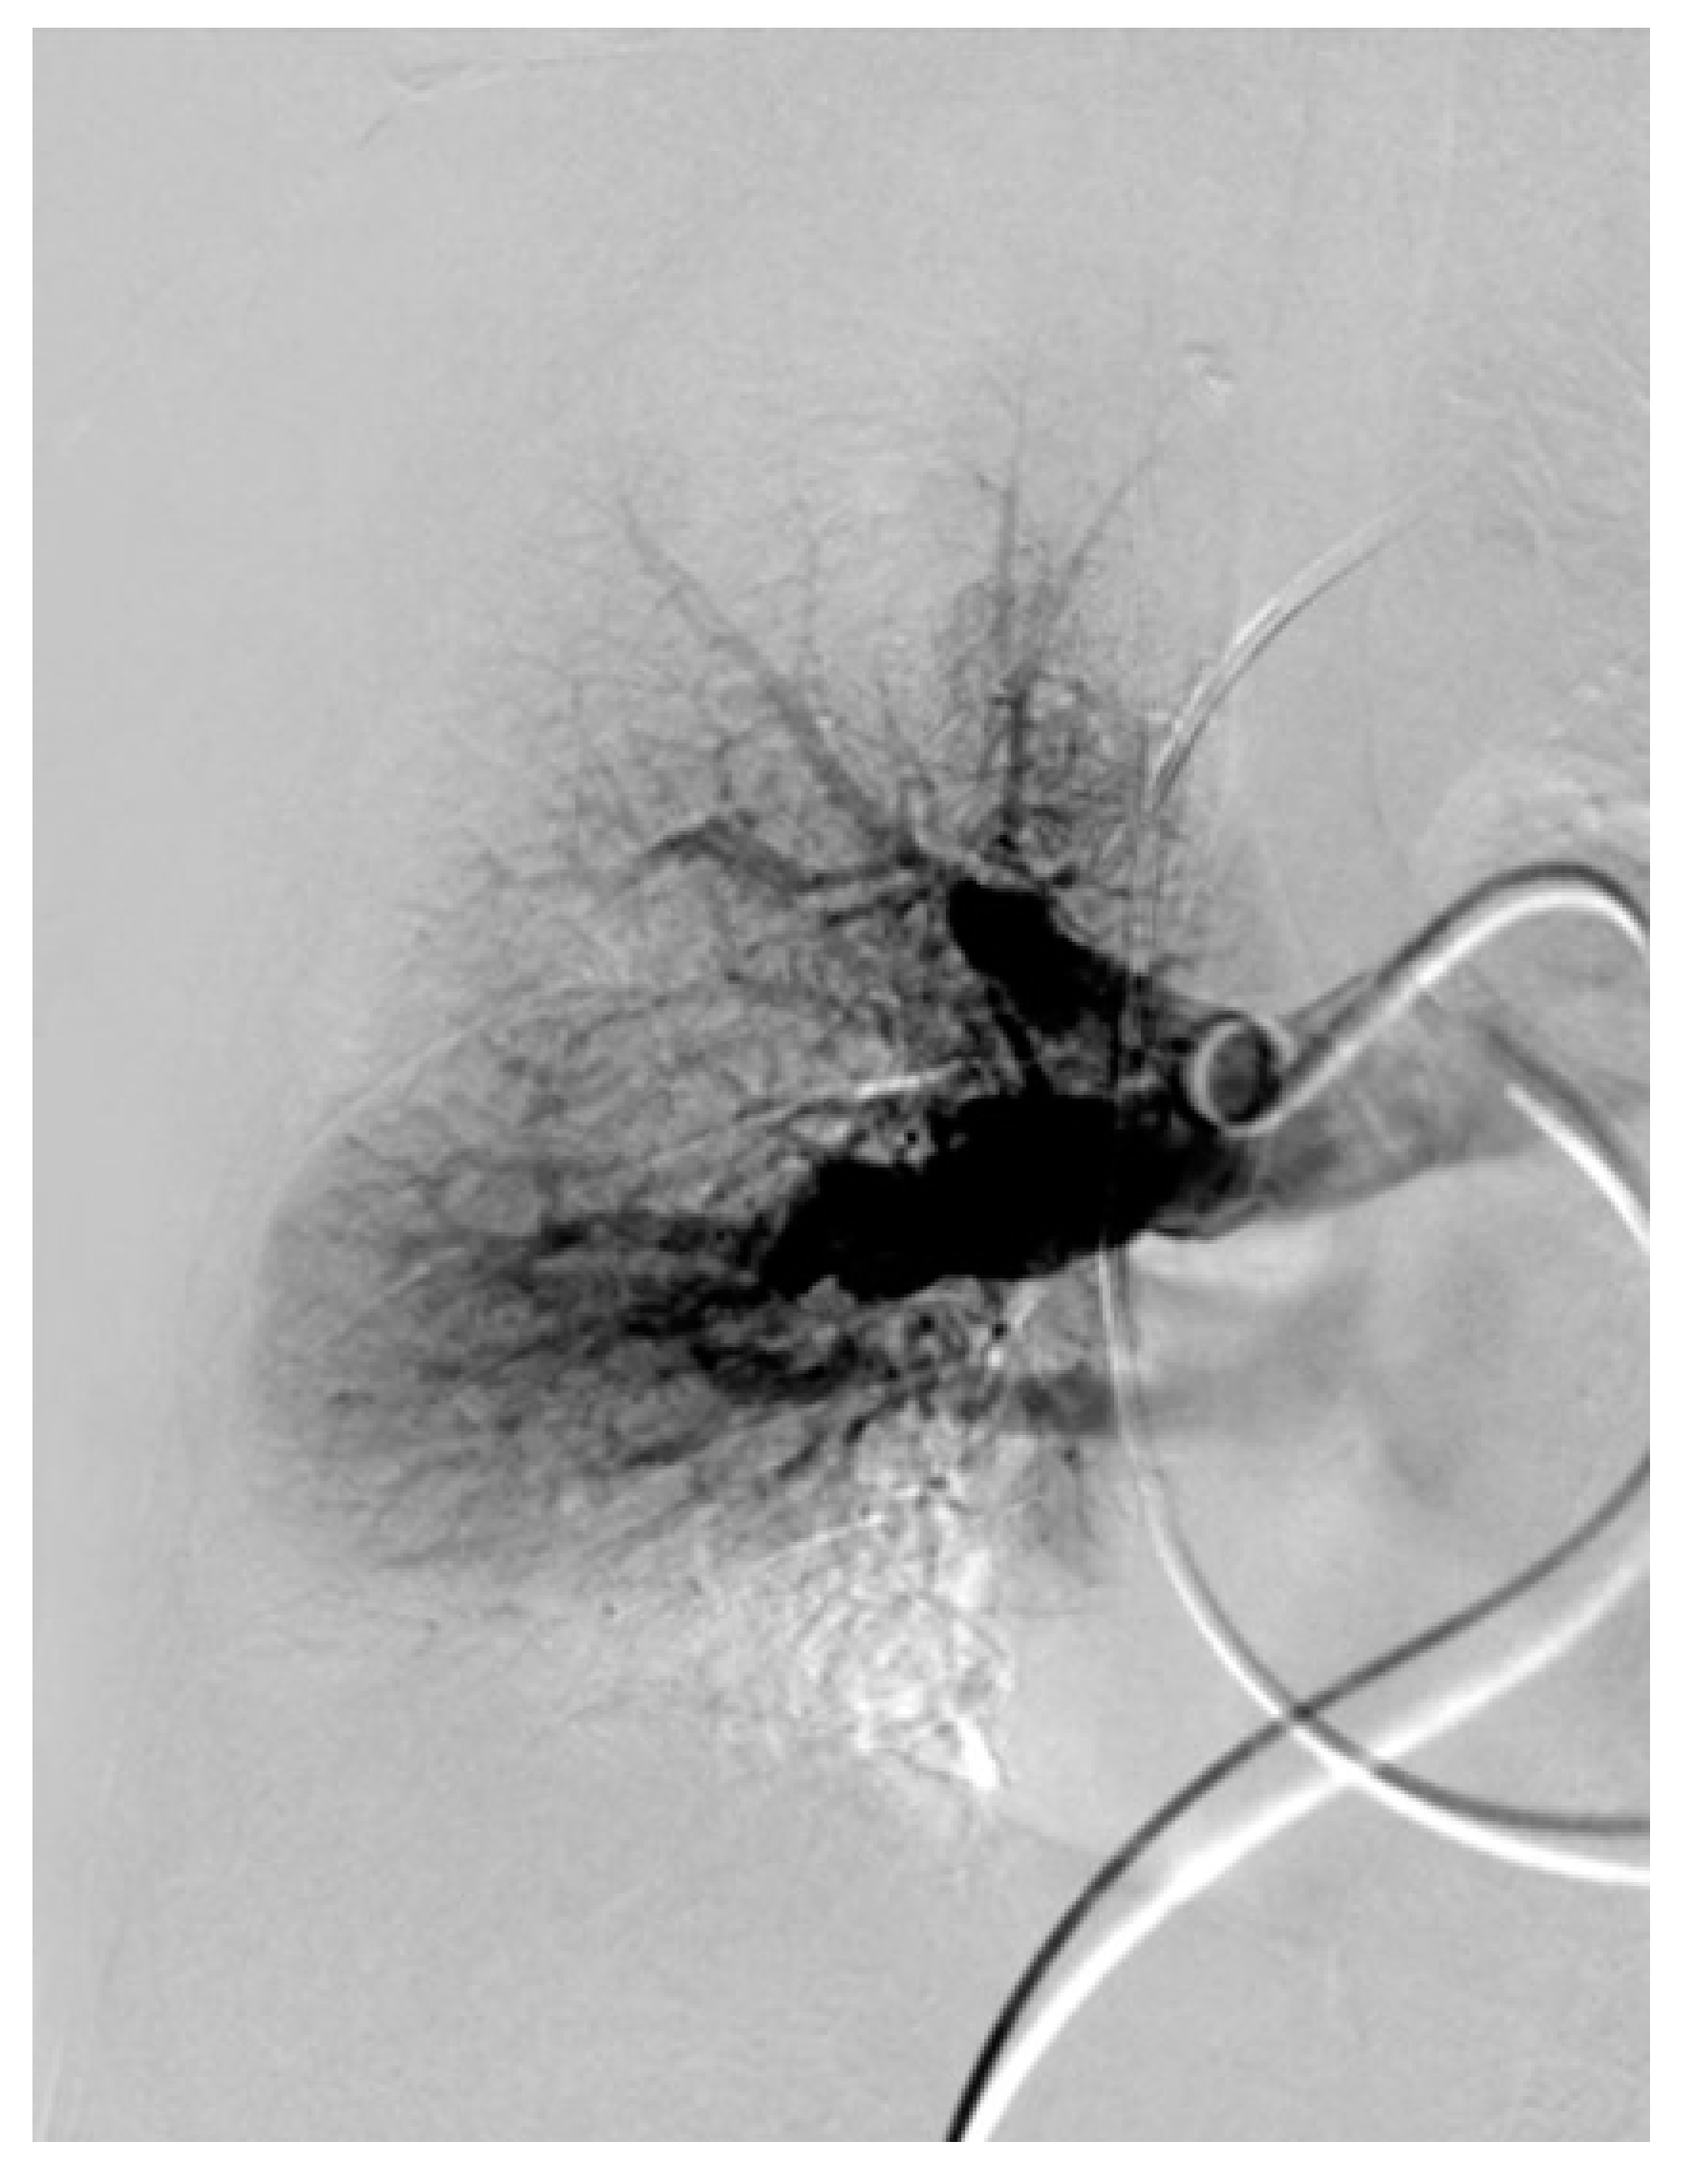

3.3. Imaging

3.4. Computed Tomography Pulmonary Angiography (CTPA)